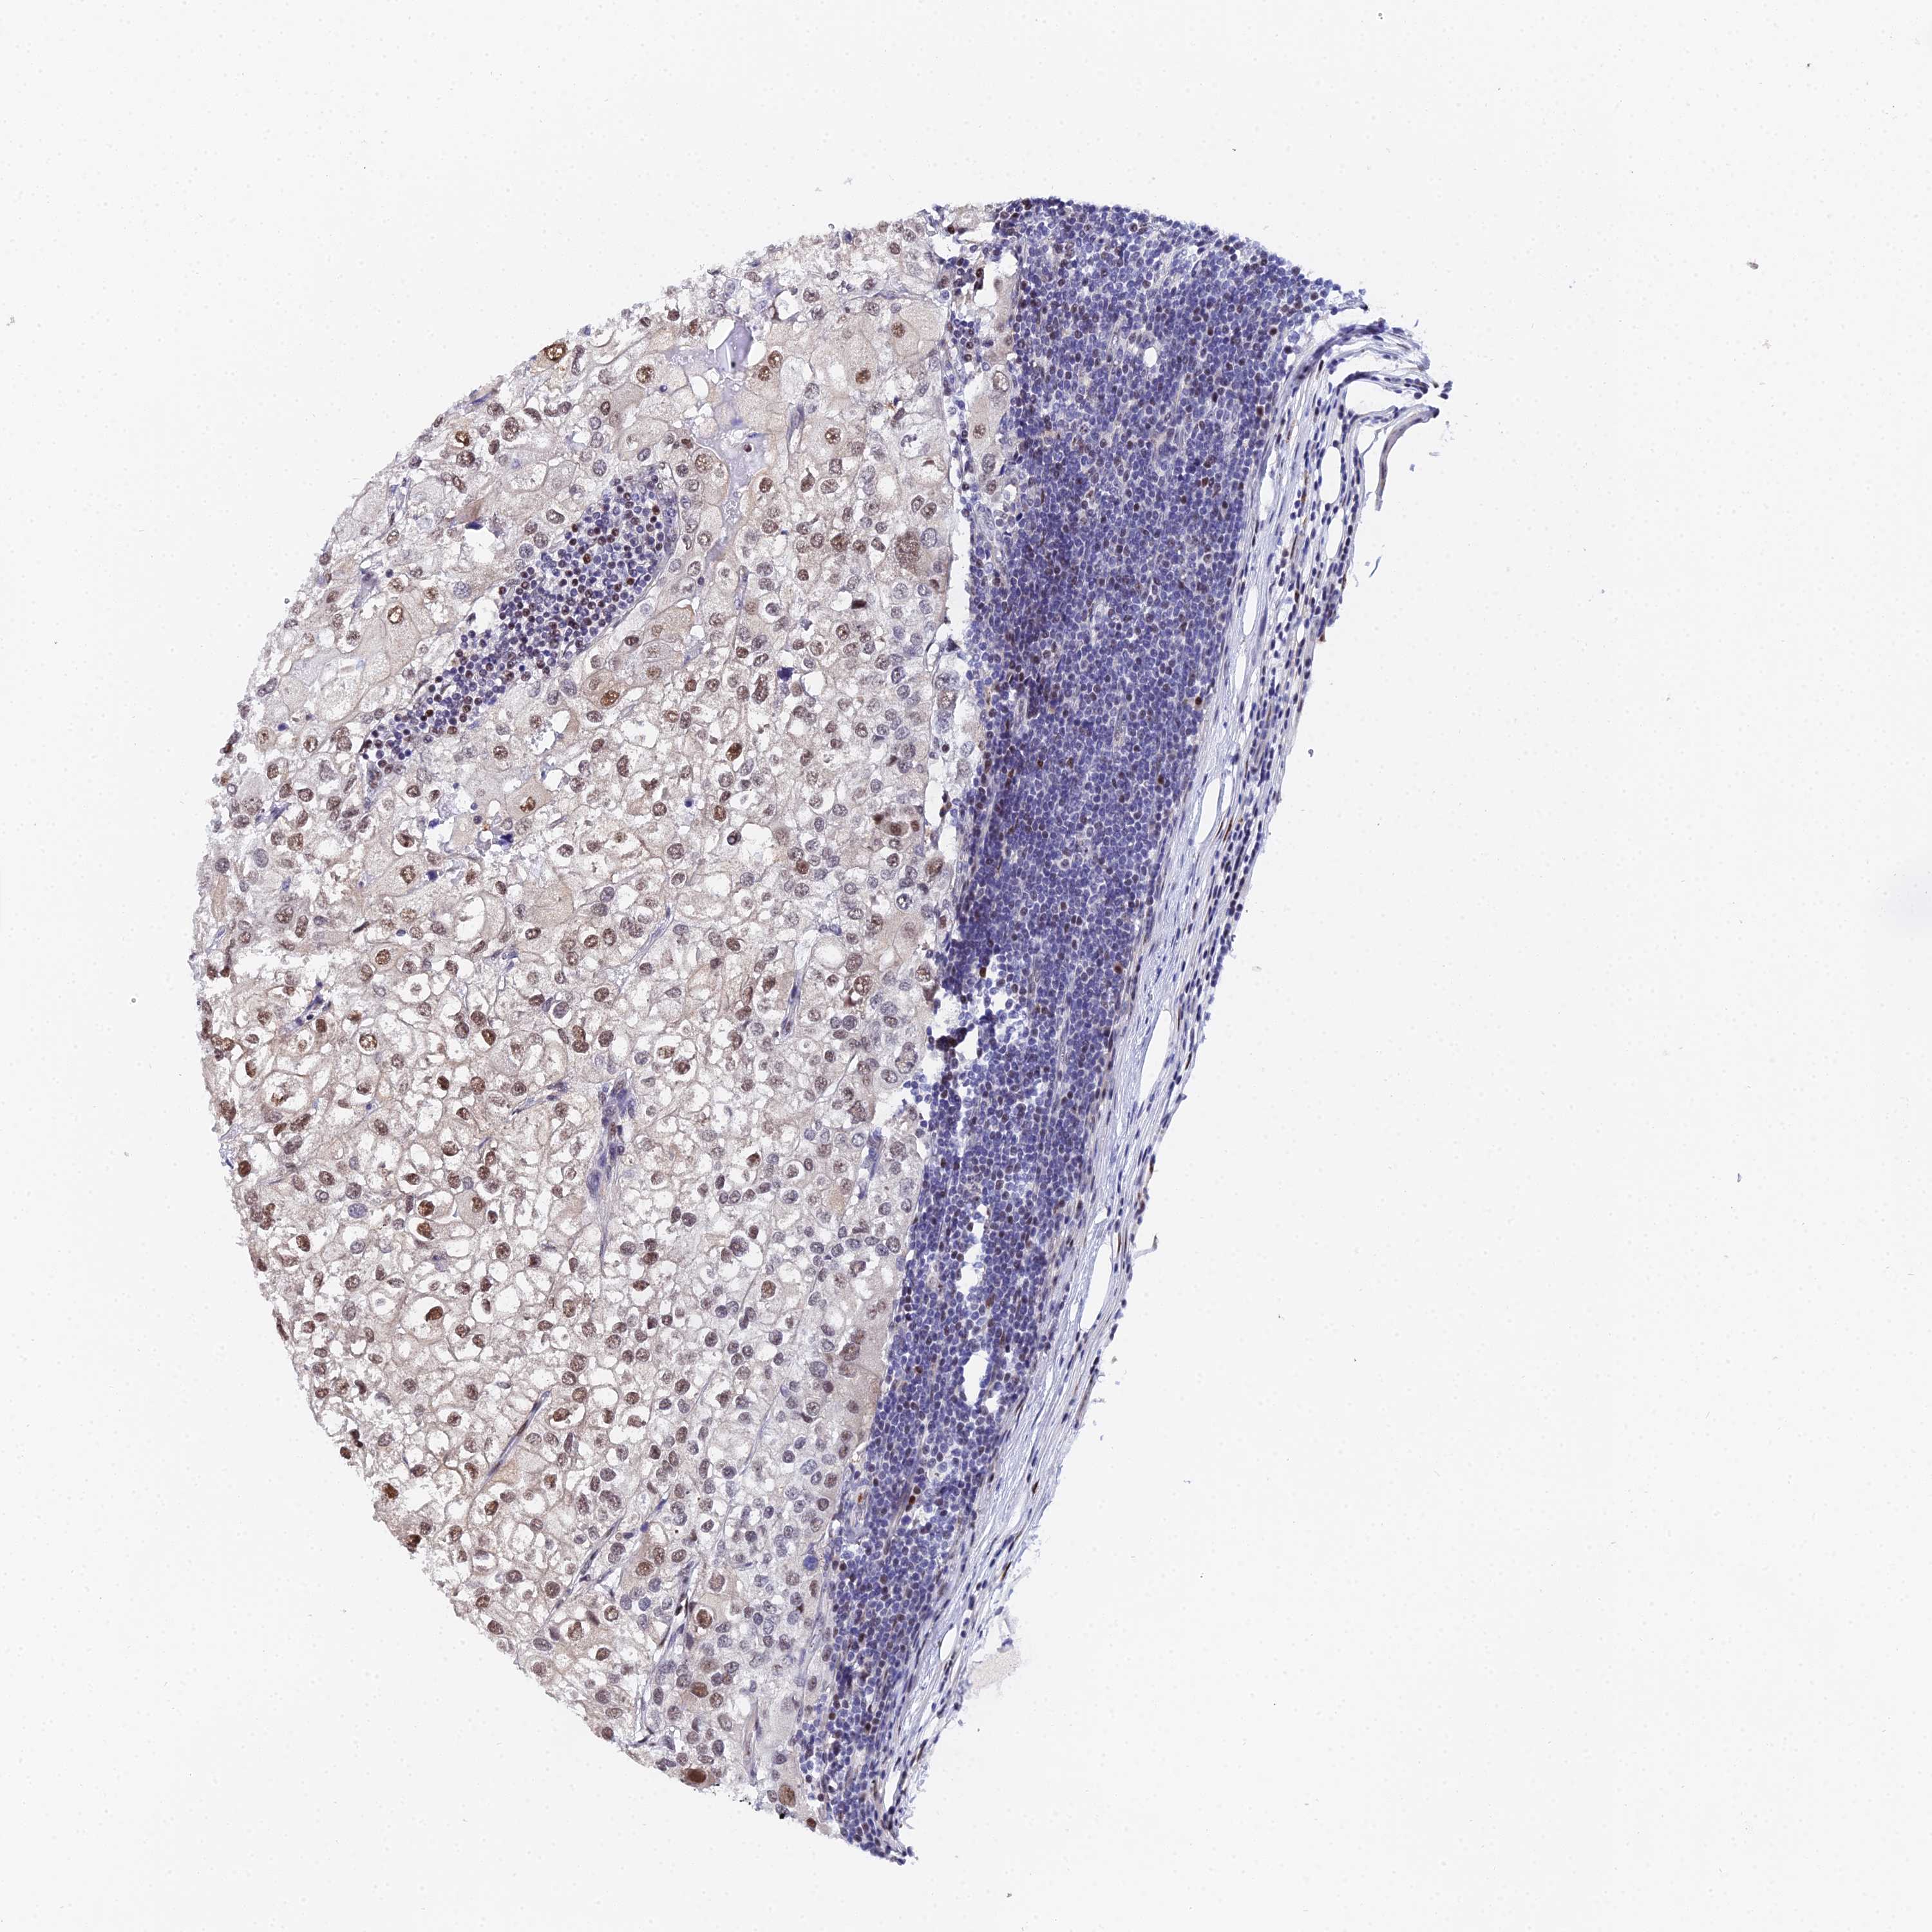

UROTHELIAL CANCER - Protein expressioni

A mouse-over function shows sample information and annotation data. Click on an image to view it in a full screen mode. Samples can be filtered based on level of antibody staining by selecting one or several of the following categories: high, medium, low and not detected. The assay and annotation is described here.

Antibody stainingi

Antibody staining in the annotated cell types in the current human tissue is reported as not detected, low, medium, or high, based on conventional immunohistochemistry profiling in selected tissues. This score is based on the combination of the staining intensity and fraction of stained cells.

Each image is clickable and will lead to virtual microscopy that enables deeper exploration of all samples and also displays staining intensity scores, fraction scores and subcellular localization as well as patient and tissue information for each sample.

Antibody HPA045889

Staining

High

Medium

Low

Not detected

Intensity

Strong

Moderate

Weak

Negative

Quantity

>75%

75%-25%

<25%

None

Location

Nuclear

Cytoplasmic/membranous

Cytoplasmic/membranous,nuclear

Urothelial carcinoma, High grade

Urothelial carcinoma, Low grade